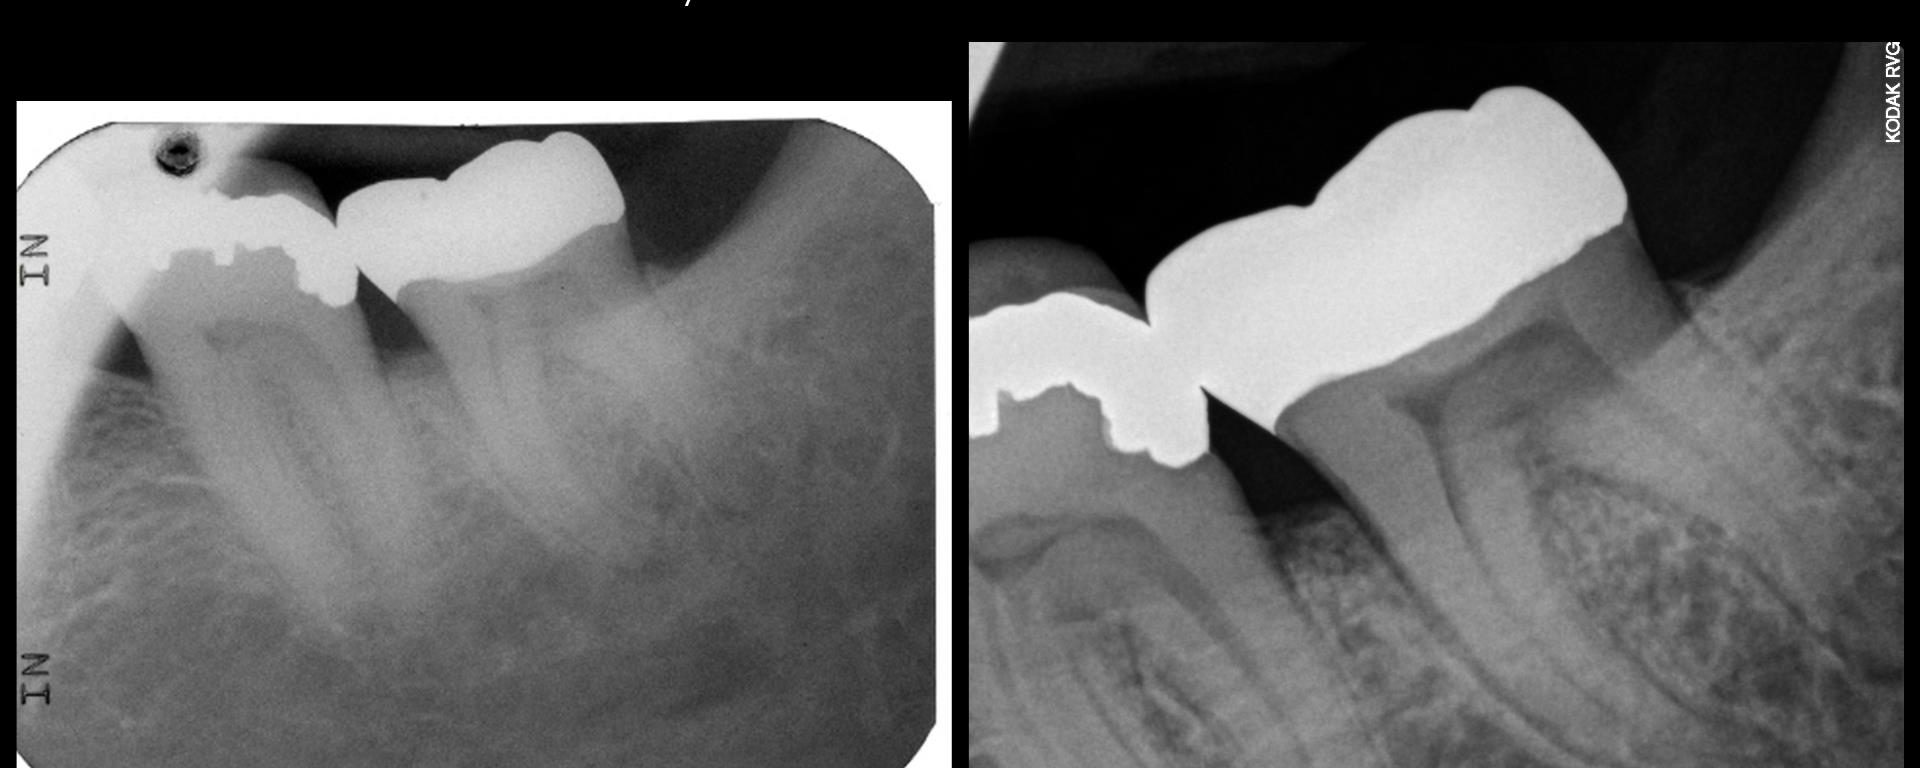

3 yr ECIR repair recall

July 20, 2018 1 comment

I struggled with the composite. I think I could do it better today but at least the repair seems to be holding. The defect went from line angle to line angle–the whole buccal face of the tooth. . gbc